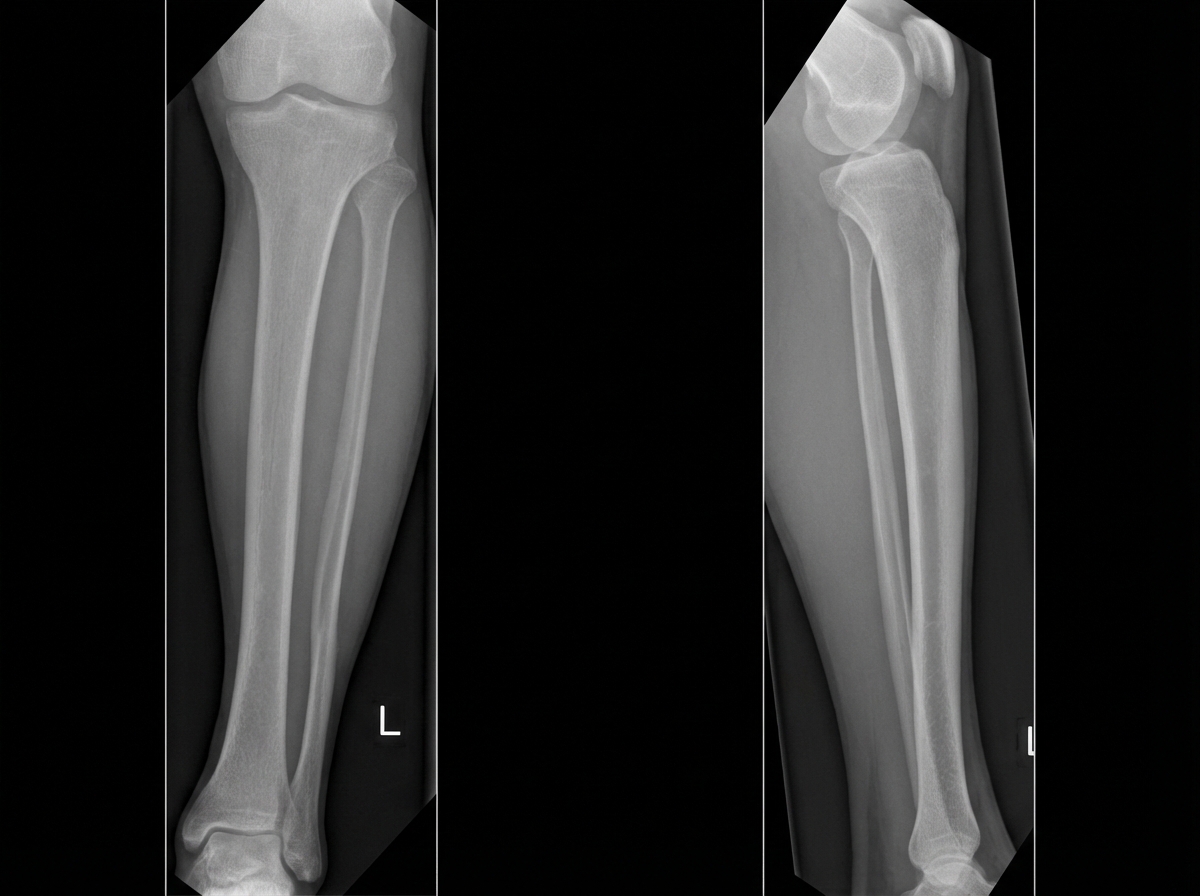

A 36-year-old man comes to the emergency department 4 hours after a bike accident for severe pain and swelling in his right leg. He has not had a headache, nausea, vomiting, abdominal pain, or blood in his urine. He has a history of gastroesophageal reflux disease and allergic rhinitis. He has smoked one pack of cigarettes daily for 17 years and drinks an average of one alcoholic beverage daily. His medications include levocetirizine and pantoprazole. He is in moderate distress. His temperature is 37°C (98.6°F), pulse is 112/min, and blood pressure is 140/80 mm Hg. Examination shows multiple bruises over both lower extremities and the face. There is swelling surrounding a 2 cm laceration 13 cm below the right knee. The lower two-thirds of the tibia is tender to palpation and the skin is pale and cool to the touch. The anterior tibial, posterior tibial, and dorsalis pedis pulses are weak. Capillary refill time of the right big toe is 4 seconds. Dorsiflexion of his right foot causes severe pain in his calf. Cardiopulmonary examination is normal. An x-ray is ordered, which is shown below. Which of the following is the most appropriate next step in management?